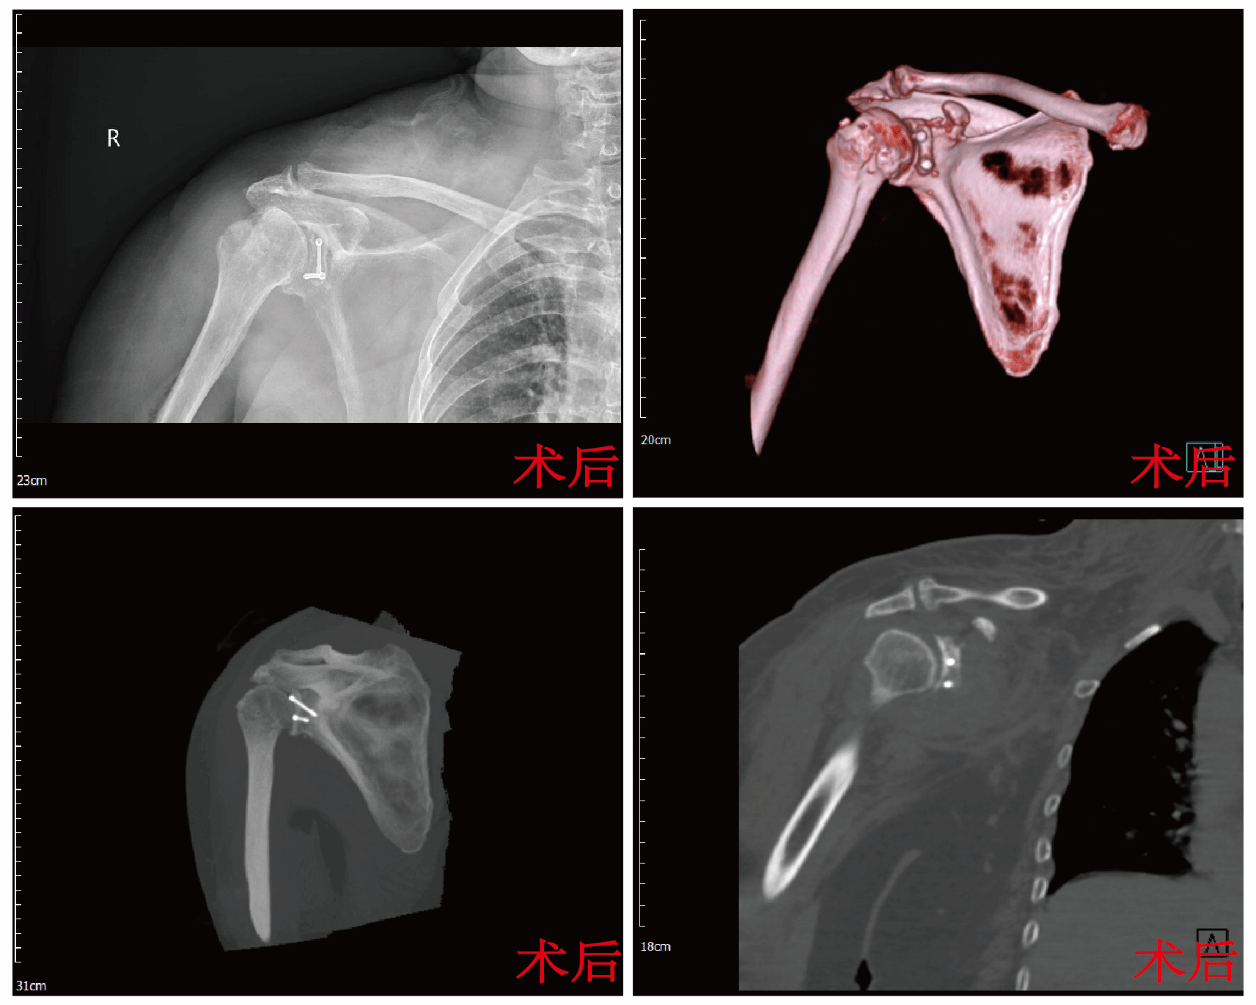

手术当日,张晨带领团队为寇阿姨实施手术,术中在高清关节镜引导下,精准锚定缝合撕裂的冈上肌与肩胛下肌,重建肩袖完整性;随后巧妙截取自体喙突骨块,精确移植固定于肩胛盂严重骨缺损处,恢复关节盂正常弧度与稳定平台;最后精细调整联合肌腱位置,为关节提供动态稳定力。手术过程顺利,目前,患者身体逐渐恢复。

“现在终于能睡安稳觉,自己梳头、穿衣了,整个人都轻松开心!”寇阿姨的感激之情溢于言表,她的笑容是对医疗团队辛勤付出的最好肯定。本例高难度复合手术的成功实施,不仅解除了患者的病痛,更具重要学术价值。手术创新性地结合国际先进的Latarjet技术与关节镜微创优势,为巨大肩袖撕裂合并严重骨缺损的复杂肩关节前脱位患者提供了更优解决方案。科室治疗团队处理疑难骨关节疾病的强大综合实力、创新精神与协作能力。